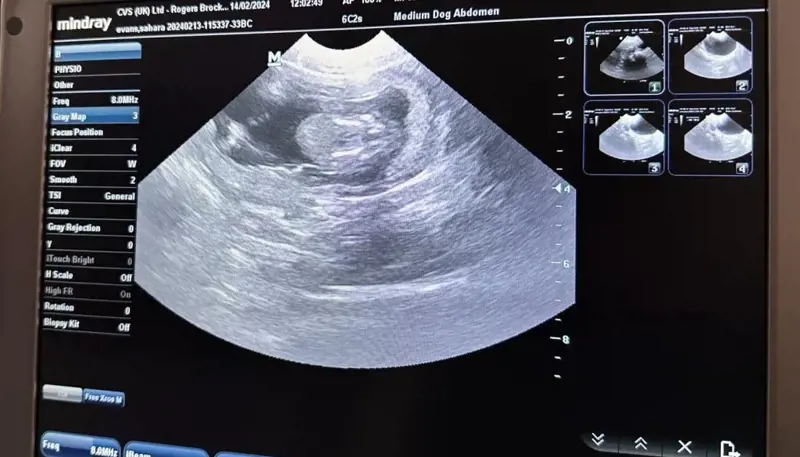

Trentham Monkey Forest has successfully carried out its first-ever ultrasound examination on a monkey called ‘Pretty’ and discovered that she is in fact, PREGNANT!

The video of the scan shows Pretty’s adorable bundle nestled safely within her womb and confirms her to be the first monkey mum of the season for Monkey Forest.

Whilst there, the team was desperate to see whether she was again, an expecting monkey mum, so asked for the ultrasound scan to be performed and were over the moon to see a beautiful bundle appear!

The team are thrilled to hear about Pretty’s healthy growing baby as usually, the first they hear or see of baby news is when a monkey mum carries her new-born bundle down from the trees in the morning when feeding the monkeys breakfast.

“This is the first time we have ever carried out an ultrasound on one of the Barbary macaques we protect here in Trentham, and we’re elated to discover that she is pregnant.